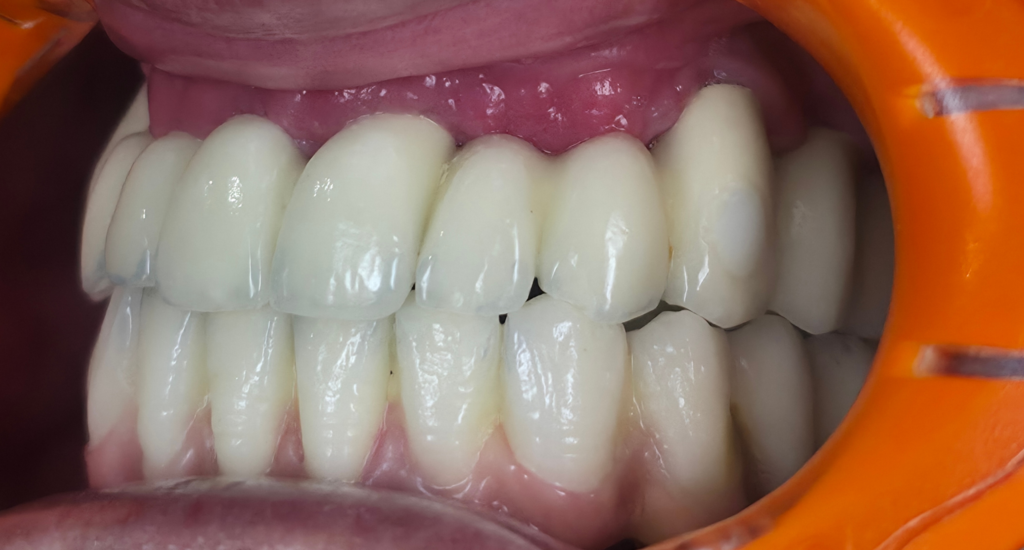

Réhabilitation esthétique après orthodontie : full-zircone & disilicate de lithium

Une jeune patiente arrive en fin de traitement orthodontique pour un déficit esthétique.

La difficulté réside dans la réalisation de prothèses différentes dans le même secteur : jongler avec la full-zircone et le disilicate de lithium.

Ce challenge fut le sujet de mon mémoire du DU d’esthétique de Strasbourg en 2008.

L’expérience et l’investissement dans le digital depuis 2017 rendent le résultat plus prévisible.